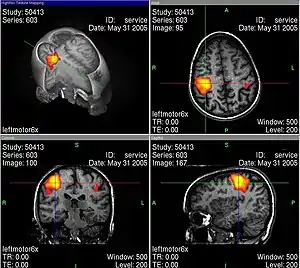

L’usage de l’imagerie cérébrale dans des programmes de recherche en neuropsychologie nécessite de bien maîtriser tous les artefacts et biais statistiques possibles, par exemple lors de l’IRMf en faisant des moyennes spatiales, temporelles et interindividuelles. La base de cet examen est de déterminer des corrélations entre certaines tâches mentales (langage, attention, mémoire…) et des activations spécifiques de zones du cerveau[30].

Les activités électriques du cerveau conduisent à des variations de tension électrique à la surface de la tête, que l'on peut enregistrer avec des appareils convenables. Les neurosciences cognitives actuelles reposent très largement sur le procédé d'imagerie par résonance magnétique fonctionnelle (IRMf). En même temps, ce genre de méthode soulève déjà une série de questions éthiques. Au moyen de l'IRMf, l'activité dans le cerveau peut être mesurée avec une bonne définition spatiale et temporelle. Cette technique conduit à des problèmes éthiques en particulier quand on trouve au moins grossièrement des corrélations entre l'activité neuronale et l'état conscient du sujet. Comment se comporter quand on sait par des méthodes neurologiques, et non par ce qu'elle en dit, qu'une personne pense à quelque chose ou le sent ?

Les images d'IRMf bien connues (voir par exemple ci-contre) sont toujours interprétées selon des modèles qui en permettent la lisibilité. Pendant une tâche cognitive, le cerveau est constamment actif dans un grand volume, et il faut trier pour obtenir des images significatives, dépourvues de toutes les activités apparemment secondaires. Ce genre de tri se fait avec une méthode de soustraction : par exemple si l'on s'intéresse à une tâche cognitive K, alors on mesure l'activité du cerveau dans une situation S1 dans laquelle K est accomplie. Ensuite, on mesure l’activité dans une situation de contrôle S2 qui ressemble à S1, mais qui n'a a priori rien à voir avec la tâche K. Finalement, on soustrait les activités mesurées dans S2 de celles mesurées dans S1, pour voir les activités corrélées avec la tâche K de façon spécifique. Illes souligne qu'il faut toujours garder en tête ces aspects interprétatifs, ce qui peut facilement passer inaperçu devant un tribunal, parce que les juristes n'ont probablement aucune compétence en neurologie.

Turhan Canli explique : « L'image d'un type d'activité basée sur une étude de mauvaise qualité ne peut pas être visuellement distinguée de celle d'une étude exemplaire. On doit être un habile spécialiste pour éventuellement remarquer la différence. C'est là que réside le grand danger d'abus des données d'imagerie auprès d'un public non éduqué, comme le jury d'une cour d'assises. Si l'on regarde les images, on peut facilement oublier qu'elles représentent des déductions statistiques et jamais une vérité absolue[32] ».